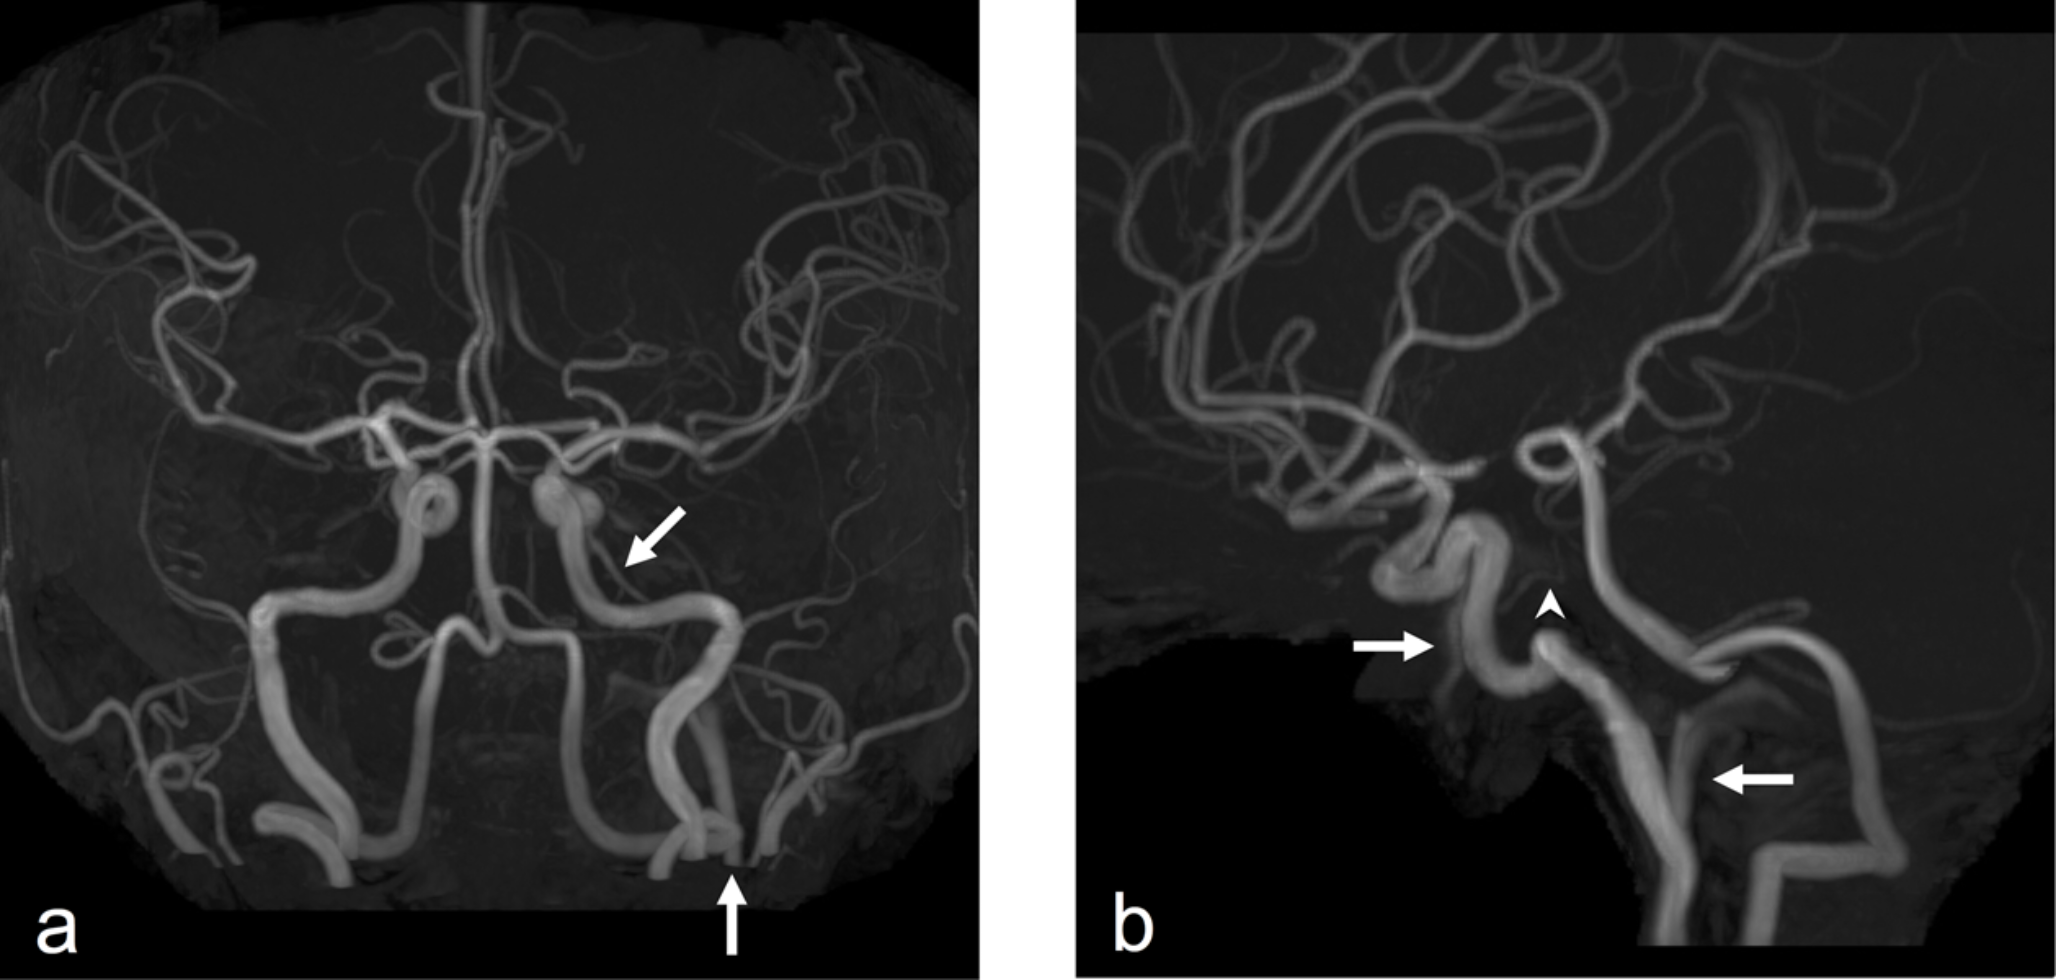

Replaced right posterior cerebral artery associated with ipsilateral superior cerebellar artery type persistent trigeminal artery variant diagnosed by magnetic resonance angiography

To describe a case in which a right replaced posterior cerebral artery (PCA) was associated with an ipsilateral superior c...

Persistent trigeminal artery variant as a duplicate anterior inferior cerebellar artery

A persistent trigeminal artery is the most common persistent carotid-vertebrobasilar anastomosis. Persistent trigeminal ar...